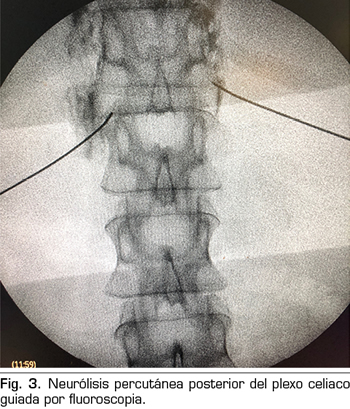

– Abordaje transcrural: el más utilizado para el bloqueo del plexo celiaco (Figura 3). El paciente se coloca en decúbito prono, identificando el cuerpo vertebral L1 y avanzando una aguja por cada lado, a unos 7,5 cm de la línea media, hasta atravesar la crura diafragmática y bloquear el plexo.

Consiste en la destrucción de las fibras que componen el plexo celiaco mediante la inyección de un agente neurolítico, prefiriéndose el uso de alcohol debido a su menor afinidad por los vasos sanguíneos, comparado con el fenol. El abordaje clásico más utilizado es el transcrural bilateral por vía posterior, guiado por fluoroscopia o TAC.